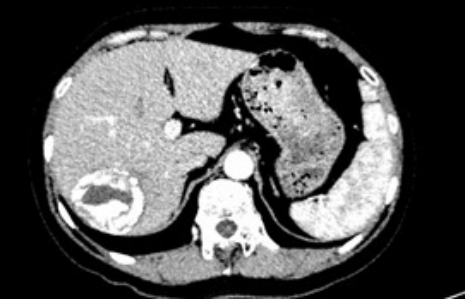

潘阿姨(化名)怀揣着忐忑的心来到了ac米兰官网中文网站一院,在此之前,阿姨因体检发现肝占位,辗转多家医院,但都无法得到明确的诊断。患者既往10年前曾有过牛羊养殖史,病灶巨大且位置刁钻,通过增强CT发现患者病灶大小约6.0×4.7cm,位于Ⅵ、Ⅶ段,毗邻着门静脉右支,手术难度大,风险高。为此,阿姨深受困扰,直到她慕名来到ac米兰官网中文网站一院门诊找到姜洪池教授团队。

入院后,通过AFP、PIVKA-II及彩超的影像学检查,排除了恶性病变的可能,最终诊断为肝包虫病。考虑到肿物为肝脏良性病变,且保留肝脏功能对患者至关重要,姜洪池教授团队决定采用腹腔镜方式,暨通常所讲的“微创方式”进行治疗。经过术前一系列准备,在姜洪池教授、金也医生、刘嘉铭医生,以及手术室贺轶宁护士、国鹏护士熟练配合下,紧贴病灶边缘,最大限度地保留了病灶附近的血管、肝蒂、正常肝组织,完整地切除了包虫病灶,成功保证了患者术后的肝功能状态。手术历时3个小时余,出血仅30ml,术后患者安返病房,目前患者已康复归家。